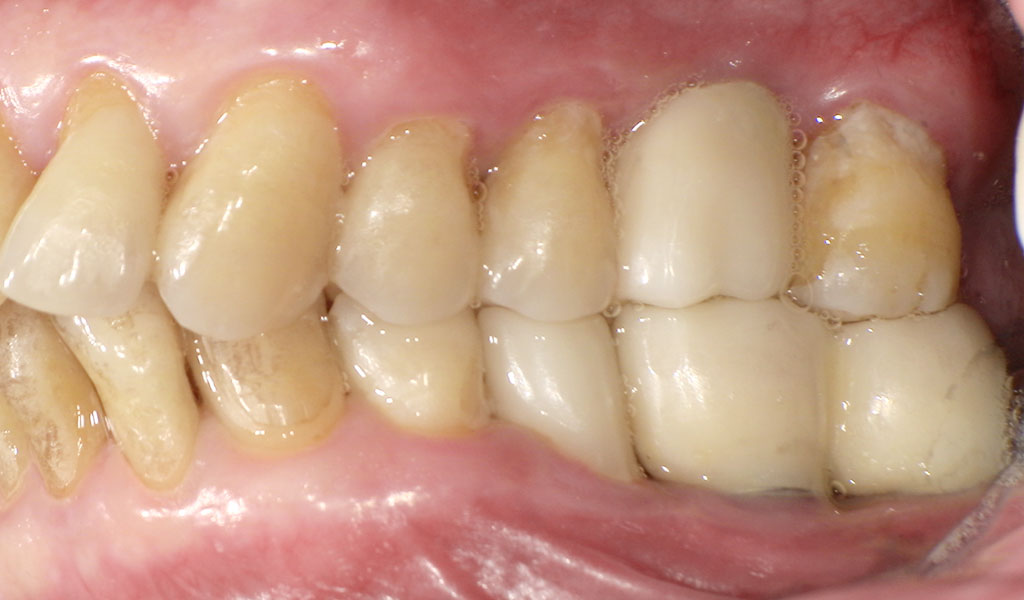

After(左上6番)

After(左下6,7番、右下5,6,7番)

After(左上6番、下6,7番)

After(右下5,6,7番)